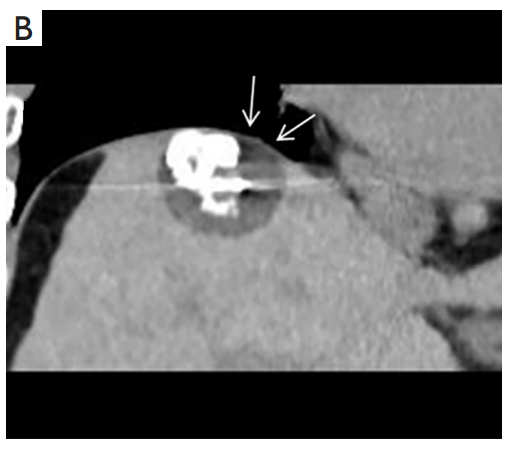

背景:肝癌是中國最常見的惡性腫瘤之一,發(fā)病率和死亡率都很高。雖然手術(shù)切除是最好的治療方法,但大多數(shù)患者處于晚期或直到住院才有手術(shù)指征。對于單個腫瘤直徑小于5厘米的患者,微創(chuàng)治療與手術(shù)切除效果相當(dāng);多個病灶小于3個,單個病灶最大直徑小于3cm;不侵犯血管、膽管、鄰近器官和遠(yuǎn)處轉(zhuǎn)移。雖然一些傳統(tǒng)消融技術(shù)方式可以使部分患者受益,但不適用于特殊部位肝癌(定義為毗鄰大血管、肝外臟器和重要結(jié)構(gòu)的腫瘤)的治療。冷凍消融作為一種相對較新的治療方式,具有明顯的冰球效果、療效好、激活抗腫瘤免疫、并發(fā)癥發(fā)生率低等優(yōu)點(diǎn),尤其適用于特殊部位肝癌患者的治療。我們的研究目的是探討CA治療特殊部位肝癌的安全性、可行性和有效性。

① 在我們的研究中,技術(shù)成功率為100%。動態(tài)增強(qiáng)MR檢查隨訪1個月,66例患者首次技術(shù)有效率為65例(98.5%),MR影像學(xué)未發(fā)現(xiàn)外周臟器損傷。中位隨訪時間14個月(范圍2-28個月)。高危部位肝癌局部腫瘤進(jìn)展率曲線:6、9、15和24個月的累積局部腫瘤進(jìn)展率分別為10.2%、16.5%、20.9%和30.5%。